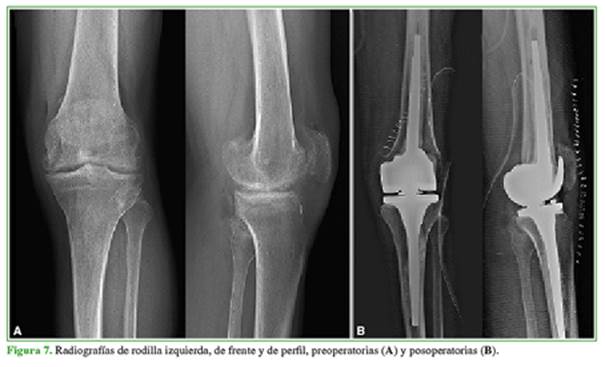

Mujer de 18 años, con artritis reumatoide juvenil y una intervención quirúrgica durante la infancia. Presenta anquilosis de la rodilla derecha en flexión de 100º, sin deformidad significativa en el plano coronal. En la rodilla izquierda, tiene un rango de movilidad de 90º, con una contractura en flexión de 30º. Tiene dificultad para deambular, subir y bajar escaleras y sentarse. El Knee Society Score (KSS) de la rodilla derecha medido antes de la cirugía era 26/50. En las radiografías, se puede observar la anquilosis ósea tanto tibiofemoral como rotulofemoral de la rodilla derecha (Figura 1).

A los 13 años de seguimiento, la paciente tiene un rango de movilidad de 90º, con una extensión completa (Figura 2).

Las radiografías no revelan signos de aflojamiento (Figura 3). El KSS en la rodilla derecha mejoró a 86/90. La paciente refiere estar satisfecha con los resultados.